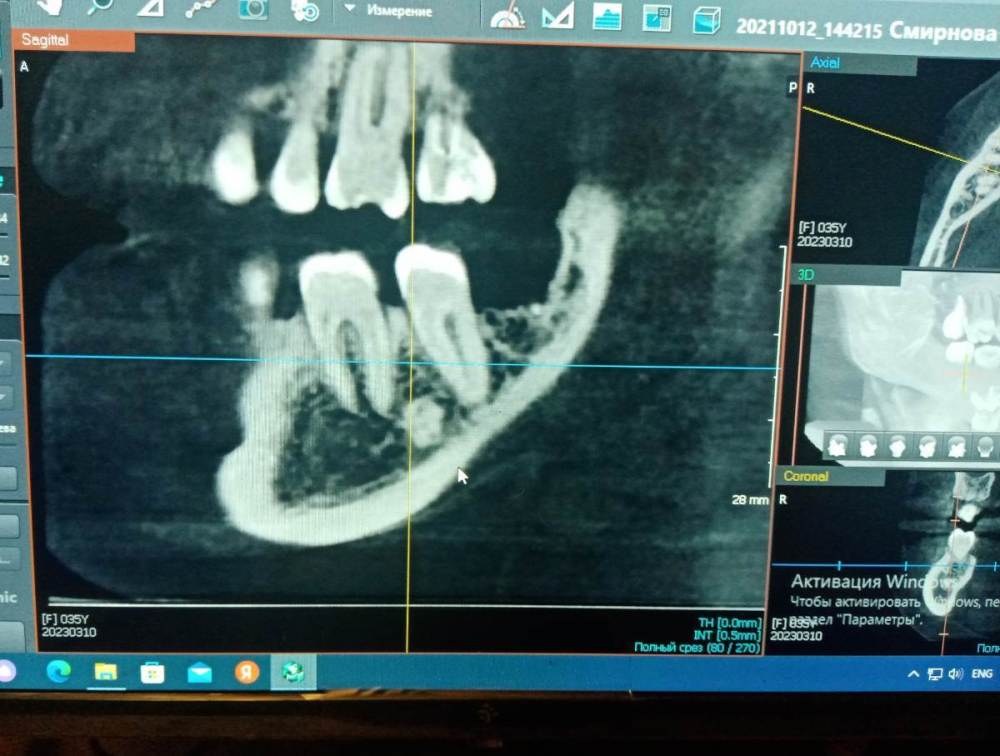

СмирноваД Опубликовано 23 марта, 2023 Автор Поделиться Опубликовано 23 марта, 2023 В общем, вскрыл мне зуб 1.2.с периодонтитом. Сделали шину,но как болела вся правая сторона, так и болит. Вечно нерв бьёт, разговаривать и глотать больно, как будто вся сторона воспалена. От шины немного легче. Ещё на КТ видно под 4. 6 зубом какое-то образование, но толком внятного ответа, что это такое, я не услышала. Уважаемые врачи, ответьте пожалуйста на пару вопросов:1.что это такое за белое на снимке и какие последствия от него могут быть. 2.И что думаете про смещение суставного диска кнаружи 5мм(заключение по мрт внчс)?Зарание Спасибо за уделённое время. Ссылка на комментарий

СмирноваД Опубликовано 23 марта, 2023 Автор Поделиться Опубликовано 23 марта, 2023 И забыла написать, что сделала ЭОД почти всех зубов с правой стороны. 4.6-25, 4.7-22 Ссылка на комментарий

АнтонТЛТ Опубликовано 23 марта, 2023 Поделиться Опубликовано 23 марта, 2023 1) Белое пятно на снимках, скорее всего просто участок более плотной кости (эностоз). Лечения и наблюдения не требует. 2) Выложите заключение по МРТ. Сделайте КТ челюстей с суставами в прикусе (без накусочной пластинки) снимок размером 16*16мм или около того. 1 Ссылка на комментарий

АнтонТЛТ Опубликовано 24 марта, 2023 Поделиться Опубликовано 24 марта, 2023 2 часа назад, СмирноваД сказал: 1)вопрос просто один, почему он образовался, этот экстоз, 2 года назад он был не таких размеров, и не так ярко выражен на снимке. Причин может быть множество. Чтобы оценить размеры и выроженность, нужно сравнивать кт с кт, а не кт с оптг. 1 Ссылка на комментарий